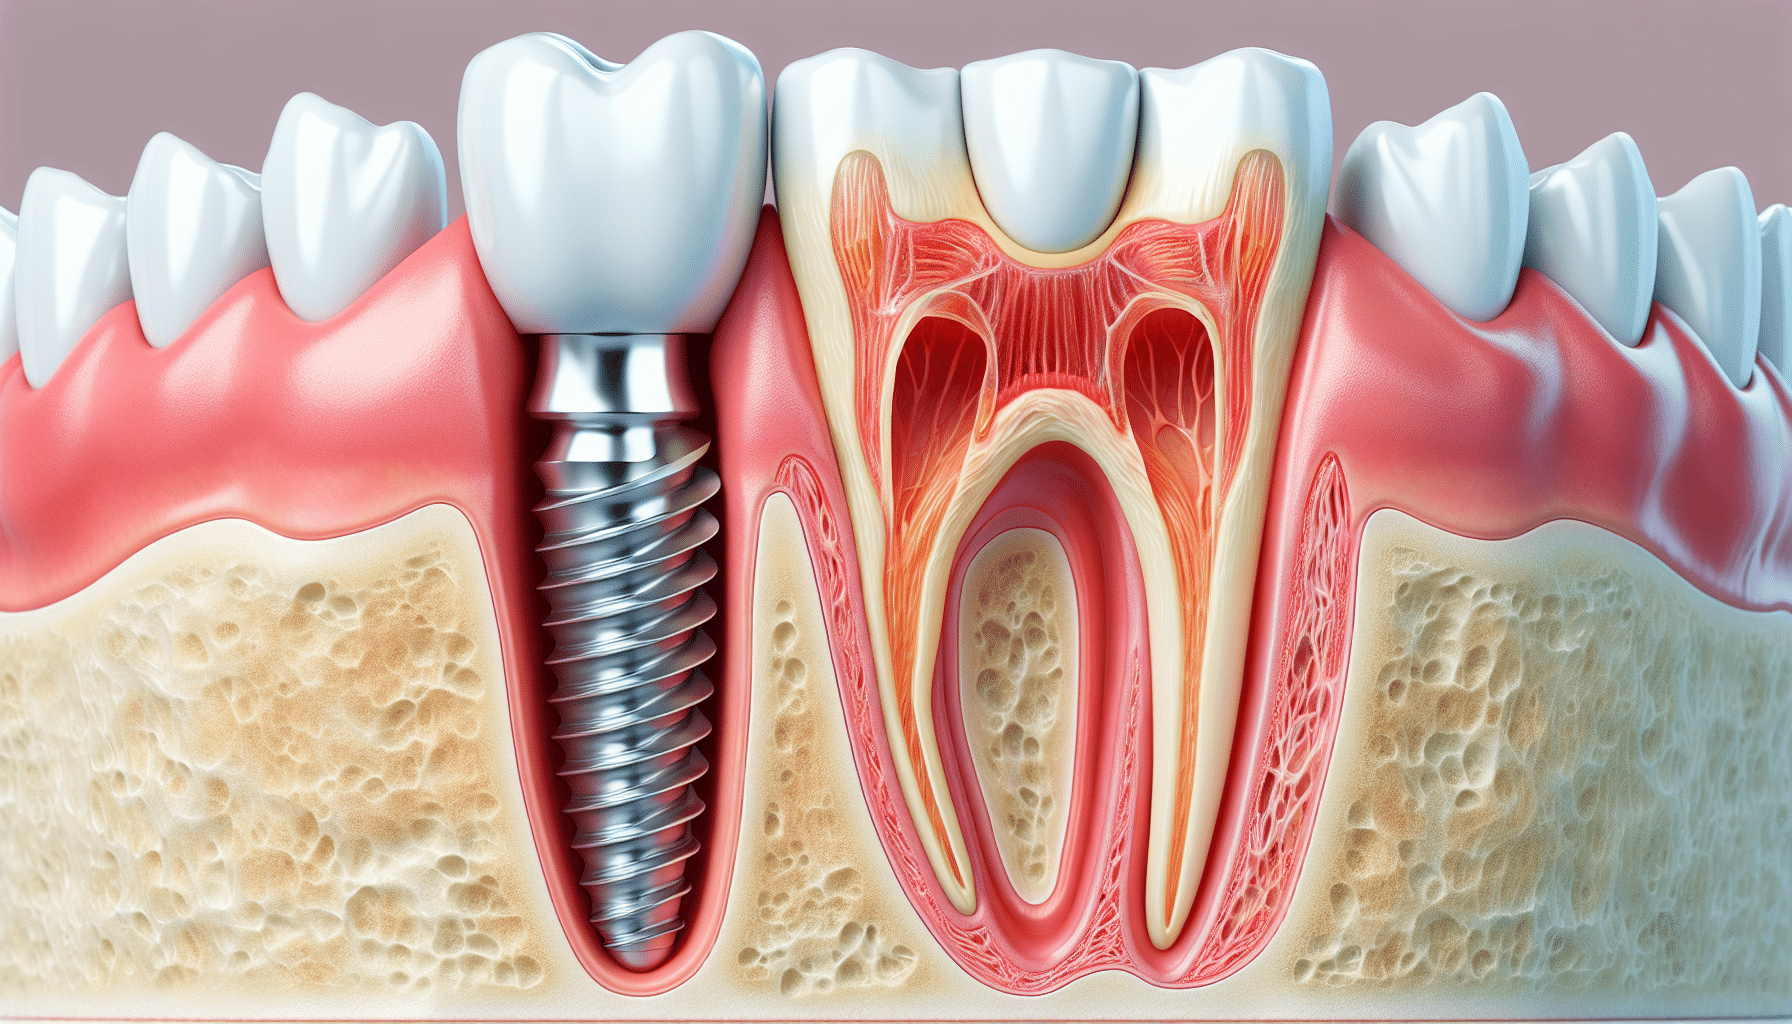

Let’s explore dental implant risks and complications together, understanding the risks, how to address them if they occur, and, most importantly, how to prevent them.

Common Dental Implant Risks and Side Effects

While dental implants demonstrate high success rates (95-97%), potential complications do exist. The most significant dental implant risks include peri-implantitis (occurring in 10-20% of long-term cases), osseointegration failure (1-2% of cases), and damage to adjacent anatomical structures, such as the inferior alveolar nerve or maxillary sinus. Research indicates smoking triples implant failure risk, while uncontrolled diabetes may reduce success rates by 30%.